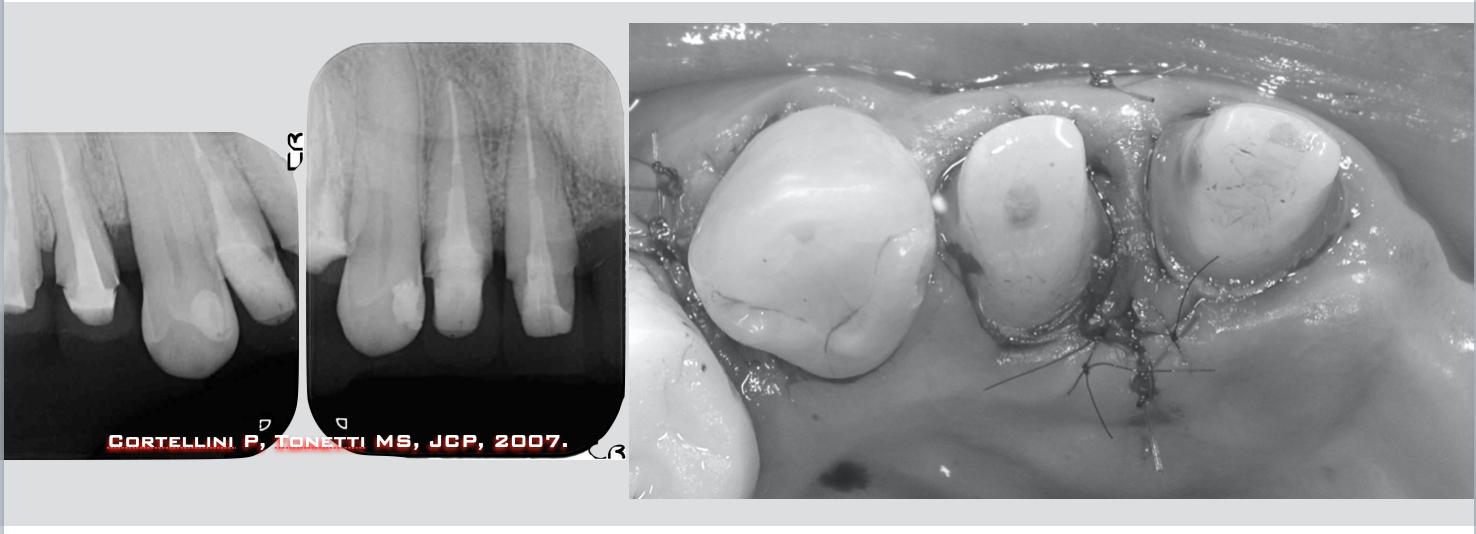

続いて下顎の犬歯の治療です。白黒でわかりにくいかもしれませんが犬歯の周囲の骨がクレーターのように溶けて大きく無くなっています(上)。

術後1年ほぼ元どおりに改善できていると思われます(下)。